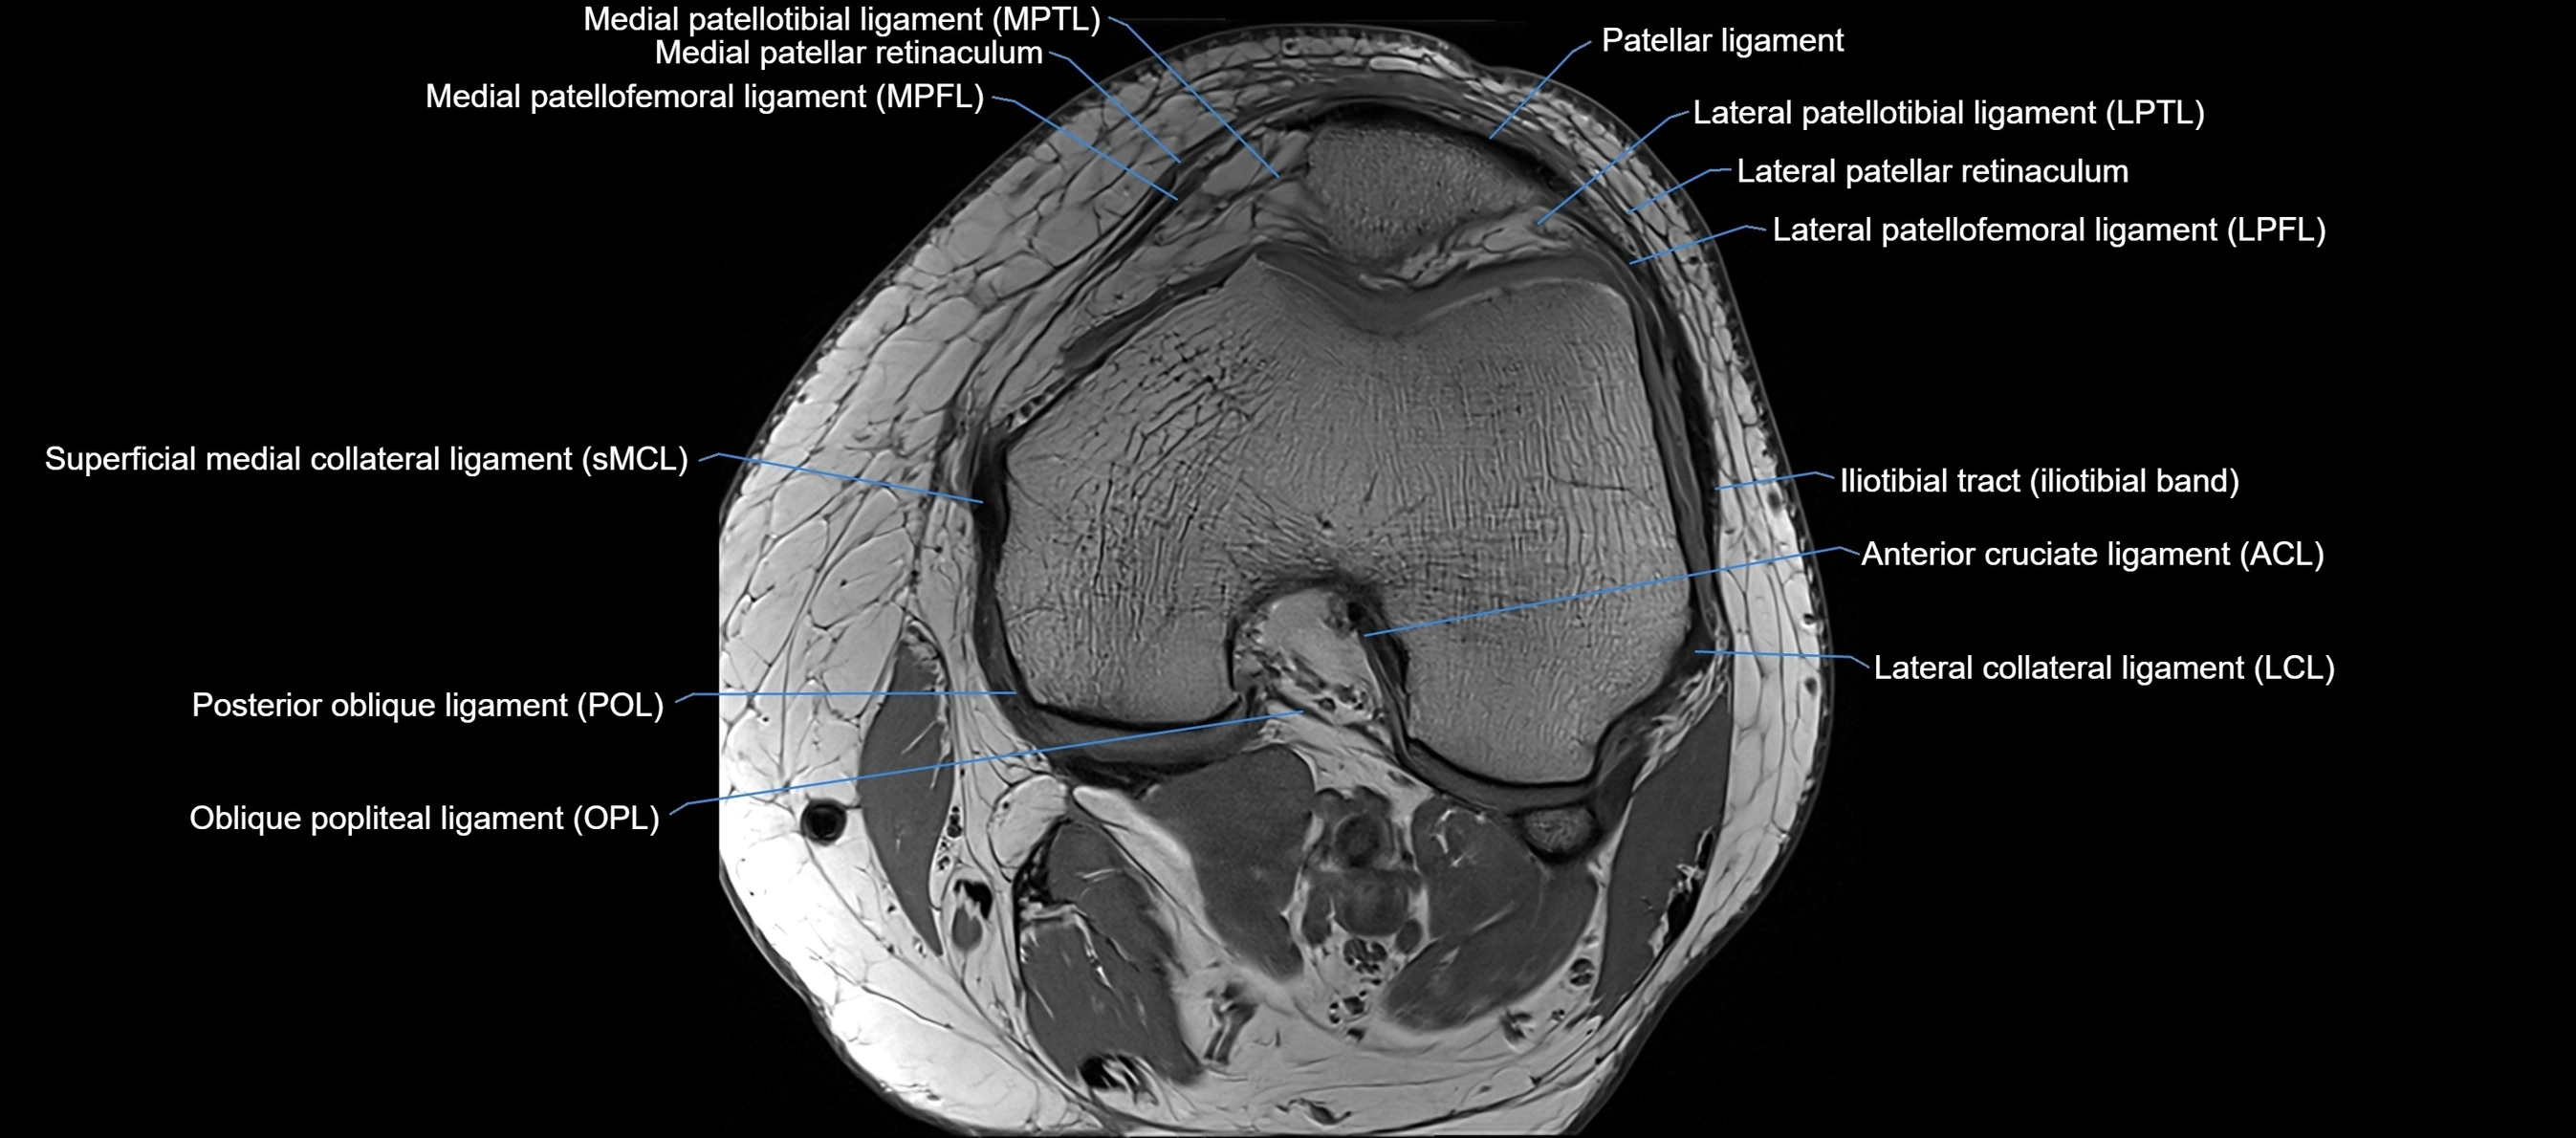

MRI Appearance

T1-weighted images:

• Normal ACL appears as a low-signal band-like structure crossing the intercondylar notch

• Surrounded by intermediate signal synovial fluid and fat planes

T2-weighted images:

• Normal ACL remains low signal

• Partial or complete tears appear as discontinuity, increased signal, or fiber laxity

MRI images

image